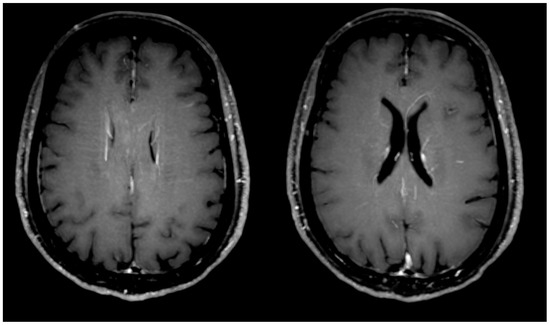

| Presence of engorgement of deep medullary veins or perivascular enhancement (Figure 2) | 3 | 13% | ||